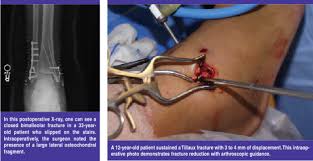

ARTHROSCOPYA DEL PIEDE - CAVIGLIA